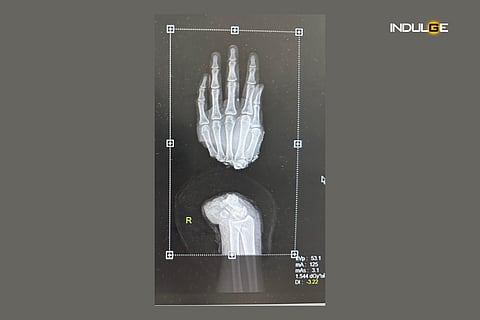

The team of doctors at Sir Ganga Ram Hospital in a complex eight-hour surgery worked swiftly to reunite the broken bones, tendons, nerves, arteries, and veins that had been cut during the accident.

"The hand is a very important part of our body, especially the right. We frequently encounter finger amputation for which we routinely perform replantation but complete hand amputation is very uncommon and was a challenge for us as there are many structures to be rejoined along with neurovascular structures," said Nikhil Jhunjhunwala, Department of Plastic Surgery, at Sir Ganga Ram Hospital.

"It took us eight hours to completely reattach his right hand, and the patient was discharged after 5 days of monitoring with the hand doing good, and the patient in a stable condition," Nikhil said.